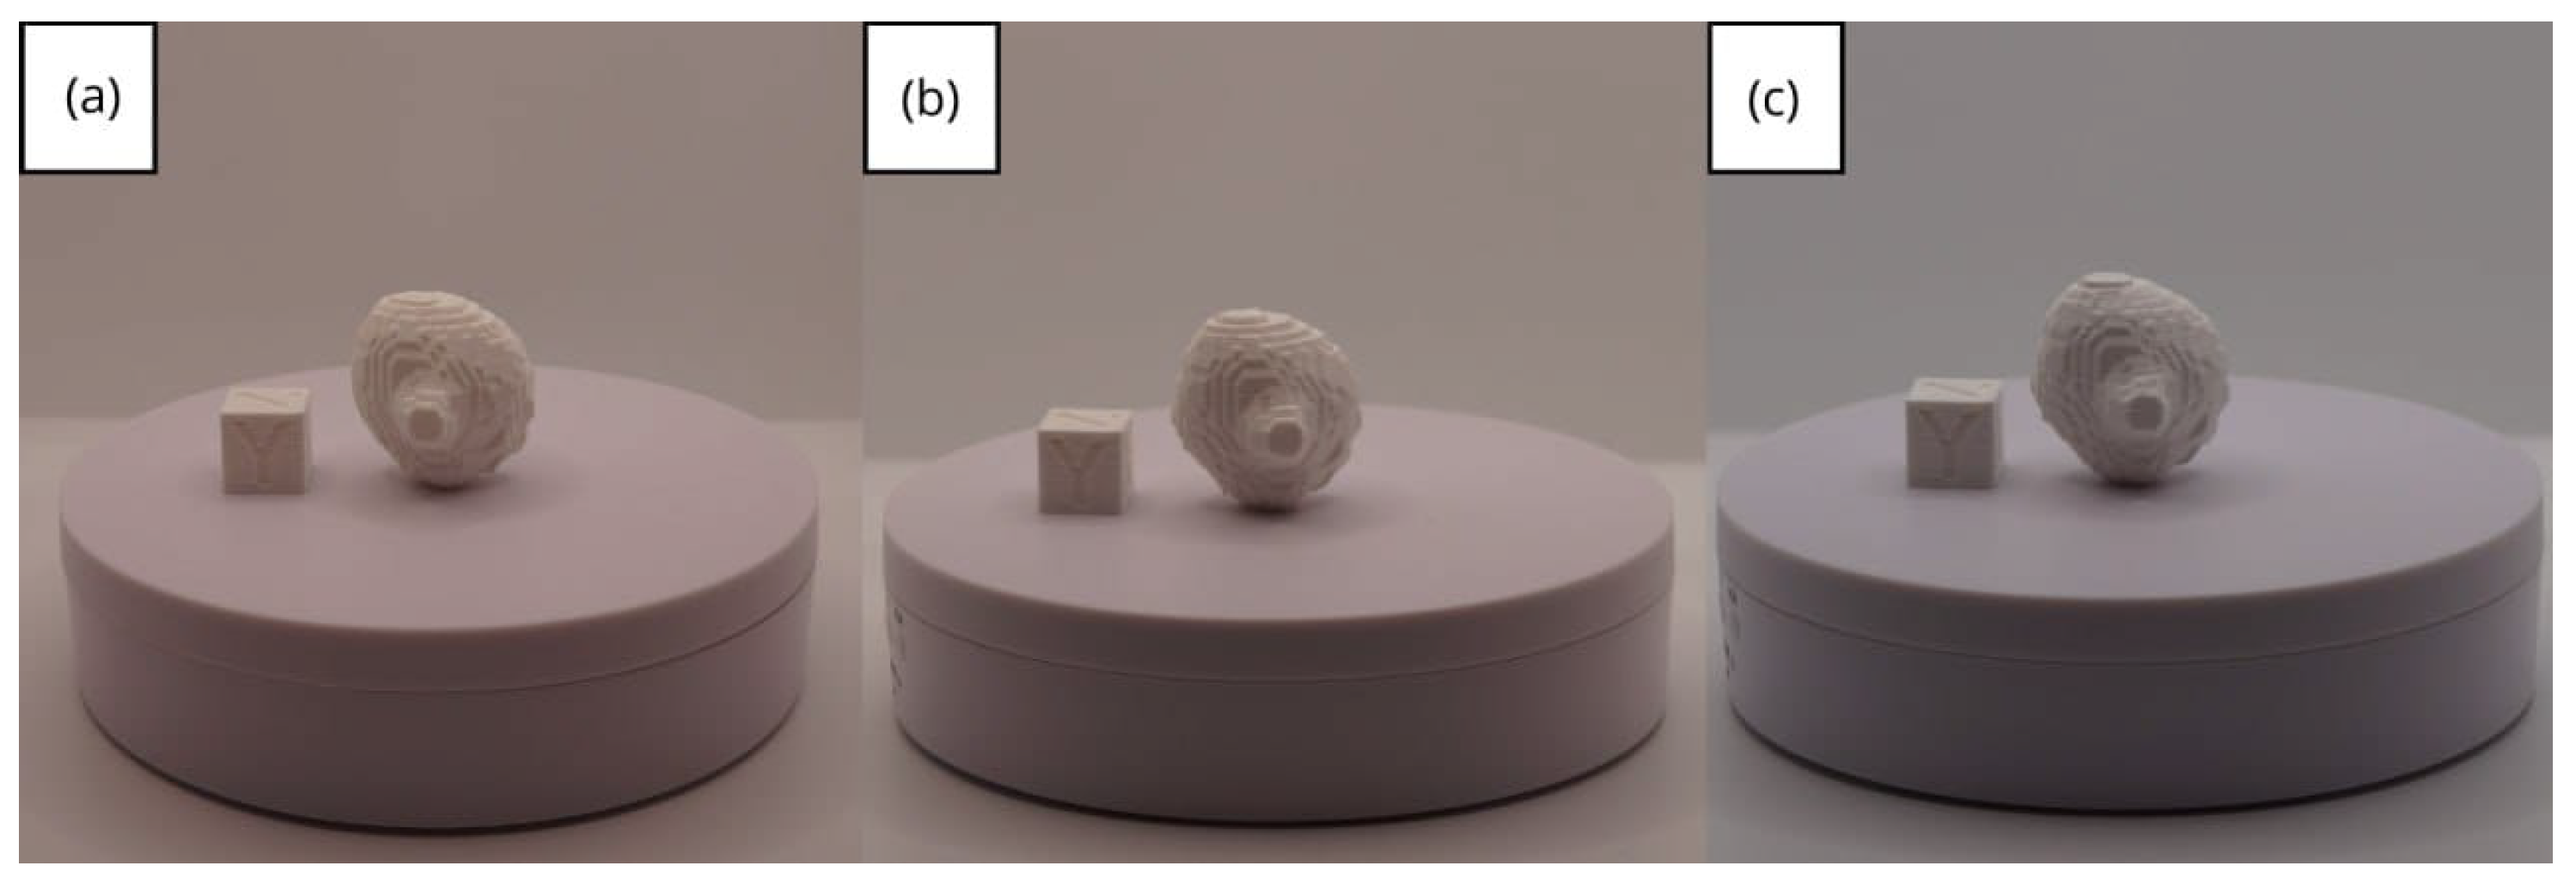

3.1.3. Final Printing

3.2. Human Lower Jaw

3.2.3. Final Printing

3.3. Human Brain Tumour

3.3.3. Final Printing